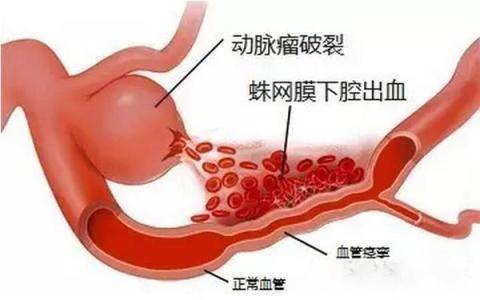

破裂出血的动脉瘤表现为蛛网膜下腔出血、脑内血肿等相应症状。

平扫—般为圆形、葫芦形或条形稍高密度影,动脉瘤壁有钙化时,CT易于显示。如动脉瘤破裂出血则表现为蛛网膜下腔出血,平扫是瘤体不易显示时,需要行CTA扫描。

造影应在出血后立刻进行,否则,出血2~3天后即发生血管痉挛,持续大约1周,此时造影,容易出现假阴性。